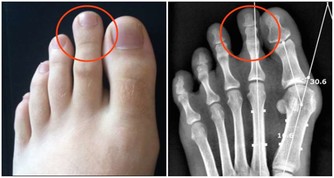

*****4、影響腎臟的健康*****

經常玩手機的人通常都是一坐就是一天,長期不活動的話就會使得體內的血液流通的比較慢,從而使得某些營養不能及時的供應到身體各個器官上,從而就會作用到腎臟上,嚴重的影響到人們的腎臟健康,出現一些腎臟疾病。